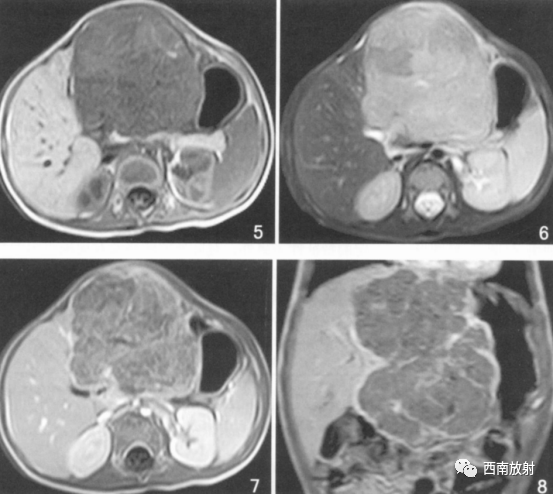

▲病例3:肝母细胞瘤。图5T1WI肝左叶巨大低信号肿块,中间见点状高信号影,考虑出血。图6为T2WI肿块呈明显高信号用哪个,增强扫描病灶内部不均匀强化,假包膜线状强化,坏死区无强化。